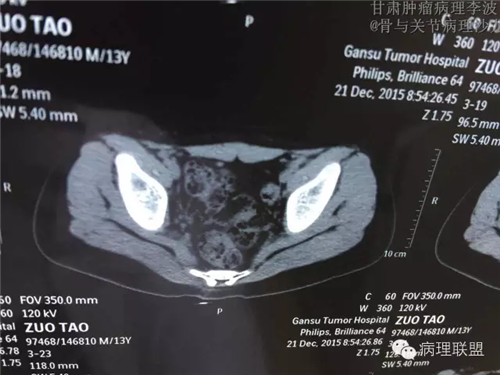

M/14 骶骨骨肉瘤-张惠箴讲解

病例由甘肃肿瘤病理 李波 提供,致谢。